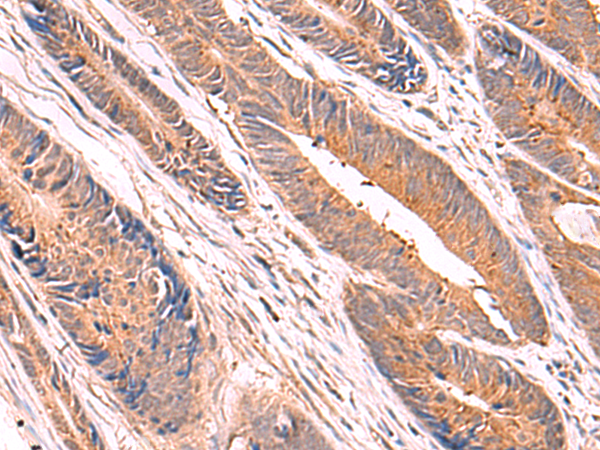

分类: 科研抗体货号: P04922别名: PBF; PRF1; HDBP2; PRF-1; HDBP-2; HDRF-2; Si-1-8-14应用: IHC反应种属: Human